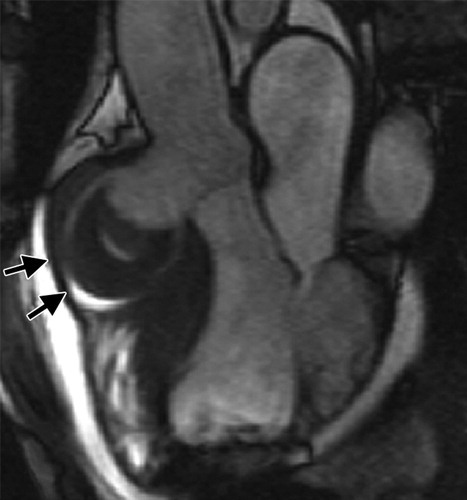

Figure 4a Nonruptured Valsalva sinus aneurysm in an 80-year-old man with chest pain and diaphoresis. (a, b) Oblique coronal (a) and oblique axial (b) balanced SSFP MR images show a 6.7-cm aneurysm (arrows) originating from the right coronary cusp and extending toward the right ventricle. (c, d) Axial contrast-enhanced ECG-gated CT images, obtained with soft-tissue window settings (c) and narrowed soft-tissue window settings (d), 3 days after patch repair, show a small leak of contrast material (arrowhead in d) extending into the aneurysm (arrows).

which sinus is most commonly involved by sinus of valsalva aneurysm?

right cusp